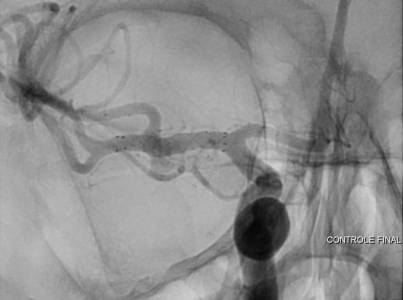

Aneurisma incidental relacionado a artéria cerebral média diagnosticado após investigação de cefaleia. Realizado tentativa de embolização com micromolas sem sucesso, sendo optado pelo tratamendo endovascular com stent redirecionador de fluxo Fred Jr 03 x 14 x 19 mm.